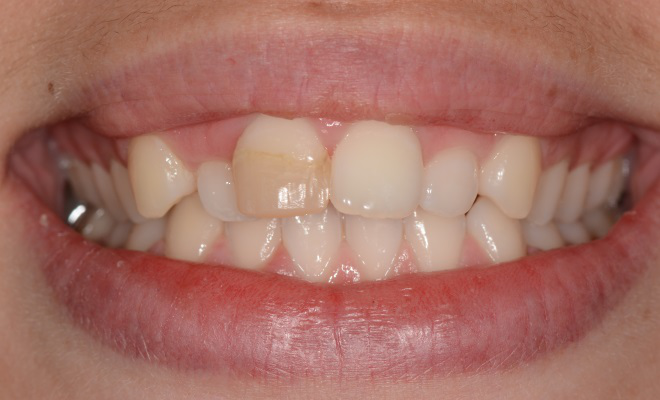

Cas 4 : 1 incisive centrale - 2 séances de 60 minutes la même journée

Une facette en céramique ne peut masquer intégralement une dent très teintée (ici orangée)